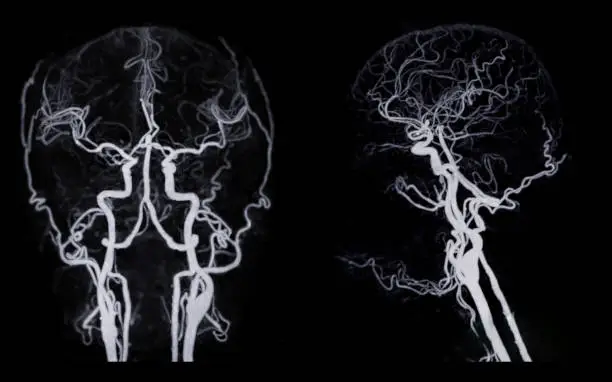

해면상 혈관종의 진단은 주로 임상적인 관찰을 통해 이루어집니다. 의사는 환자의 병력을 조사하고 종양의 모양과 크기, 촉감을 확인하여 해면상 혈관종인지 여부를 판단합니다. 필요에 따라 초음파나 MRI와 같은 영상 검사를 통해 혈관종의 정확한 위치와 크기, 주변 조직과의 관계를 확인할 수 있습니다. 특히, 내부 장기에 발생한 혈관종은 이러한 영상 검사를 통해 더욱 정확하게 평가됩니다.